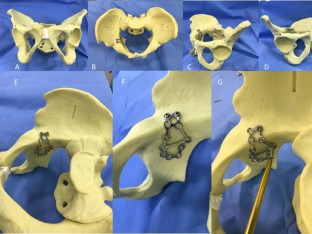

Fig. 2